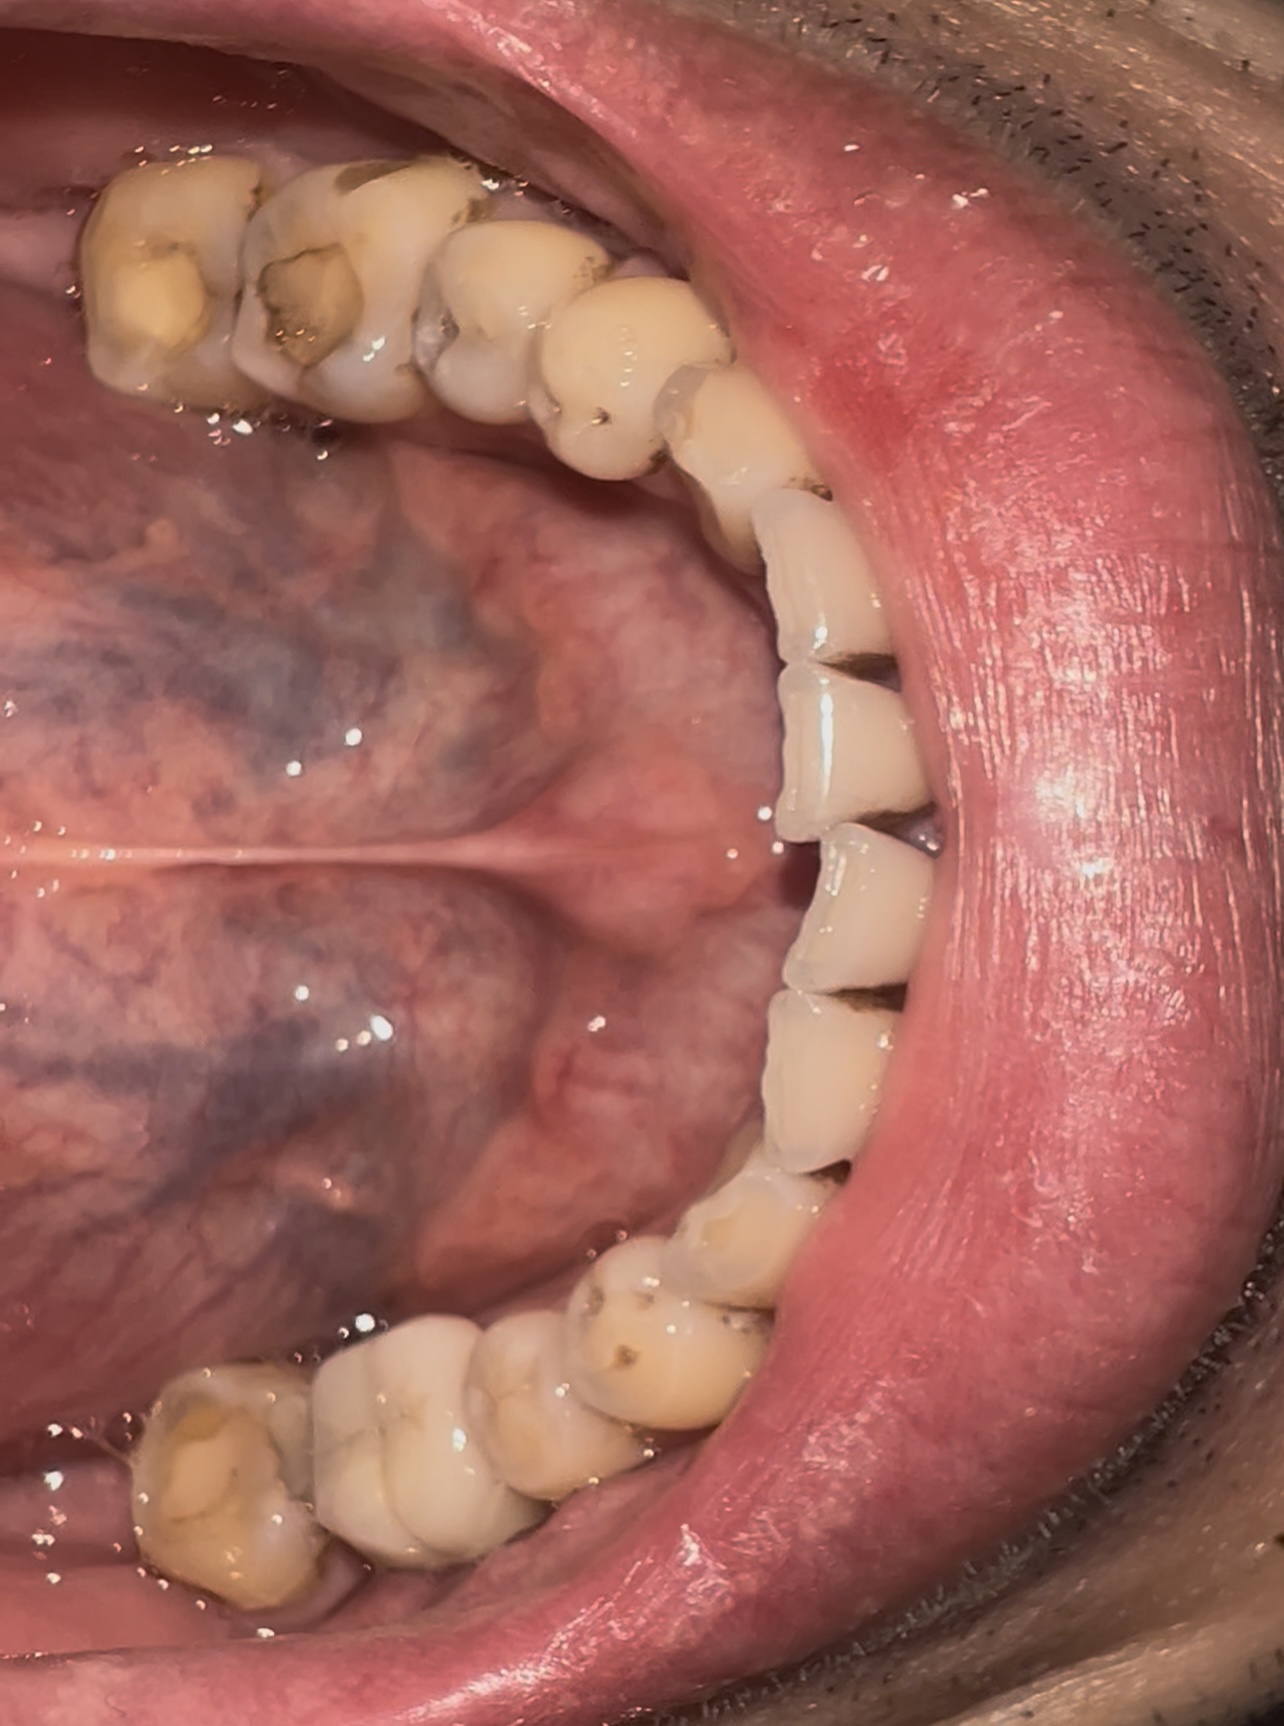

Screenshot20250[...].jpg 244Кб, 720x1600

720x1600

175879209708150[...].jpg 1246Кб, 2640x1980

2640x1980

Двач скажи, мне гг или ещё можно что-то спасти?

Зубы вроде не болят, но в стоматологии сказали везде кариес, половину зубов пломбировать...

Ещё и чистку сказали сделать, за 8к...

Крч посоветуйте что-то, не сделают ли хуже в гос.стоматологии...

Аноним 25/09/25 Чтв 13:25:03 1641753 170

хуже чем ты сделал наверно уже не будет, хз в каком там состоянии зубы, но на вскидку тебе надо удалять 2 нижних восьмерки(при том тебе скорее всего будут долбить десну чтоб горизонтальные удалить) и одну верхнюю, оставшуюся брекетами двигать если удалить огрызок, но если не готов прям щас в брекеты идти огрызки не удаляй т.к. они могут послужить основной для импланта, кроме восьмерок просто так ничего удалять не надо, очевидно это огромные бабки по нынешним временам и много усилий, если хочешь прям восстановить рот это надолго и надорого и я сомневаюсь что ты что то из этого потянешь, для человека который себя так запустил я вобще удивлен что тебя такое волнует или тебя сбил камаз и ты очнулся в теле этого бича маргинального? там наверно еще и десны воспалены(так что после чистки и заделывания кариеса к парадантологу пиздуй), действительно сперва чистка(8к это в каком городе? в нск 3,5 в гос стоматологии) и лечение кариеса, а потом..ну я бы задумался в сторону путешествия в другую страну для лечения типо дешевле, слышал краем уха про такое но подробностей не знаю, ну а так скорее всего это протезирование и видимо оно будет упираться в твои бюджеты чем дороже тем больше своих зубов или то что от них осталось сохранишь, ну а так это риально пиздец, даже у бамжей с зубами лучше